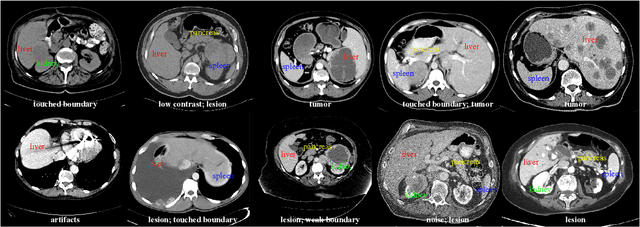

Abstract:With the unprecedented developments in deep learning, automatic segmentation of main abdominal organs (i.e., liver, kidney, and spleen) seems to be a solved problem as the state-of-the-art (SOTA) methods have achieved comparable results with inter-observer variability on existing benchmark datasets. However, most of the existing abdominal organ segmentation benchmark datasets only contain single-center, single-phase, single-vendor, or single-disease cases, thus, it is unclear whether the excellent performance can generalize on more diverse datasets. In this paper, we present a large and diverse abdominal CT organ segmentation dataset, termed as AbdomenCT-1K, with more than 1000 (1K) CT scans from 11 countries, including multi-center, multi-phase, multi-vendor, and multi-disease cases. Furthermore, we conduct a large-scale study for liver, kidney, spleen, and pancreas segmentation, as well as reveal the unsolved segmentation problems of the SOTA method, such as the limited generalization ability on distinct medical centers, phases, and unseen diseases. To advance the unsolved problems, we build four organ segmentation benchmarks for fully supervised, semi-supervised, weakly supervised, and continual learning, which are currently challenging and active research topics. Accordingly, we develop a simple and effective method for each benchmark, which can be used as out-of-the-box methods and strong baselines. We believe the introduction of the AbdomenCT-1K dataset will promote future in-depth research towards clinical applicable abdominal organ segmentation methods. Moreover, the datasets, codes, and trained models of baseline methods will be publicly available at https://github.com/JunMa11/AbdomenCT-1K.